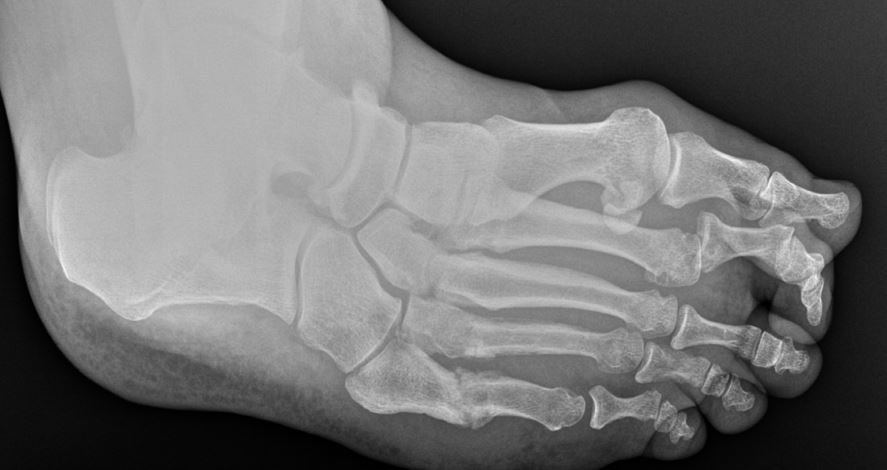

I think the interesting thing here is - do you need a 3V for this patient. My partner seems to order nothing but 2V. In time - you'll see that DP view and be pretty confident the toe is completely subluxated whether you have the oblique or not, but I like that oblique for showing this to the patient.

-The oblique view shows a number of things. The first is the subluxation ie. its up, the contracture within the toe. Additionally, the metatarsal head itself appears larger than the other heads and again the density is irregularity. The joint space seems decreased though the toe is malpositioned which contributes to this.

My last random thing though - look for these things though but go into the room with an open mind. This especially applies to trying to put everyone into a cavus/planus box before you walk into the room. Other thing - x-rays often "understate" (or is it our interpretation/perception) how large a patient's bunion will appear to be clinically. Also, go into the room considering how good a job your tech did taking the x-rays. This is especially relevant for post-ops and there's incredible value to trying to get your tech to take as true a weight-bearing view as possible.